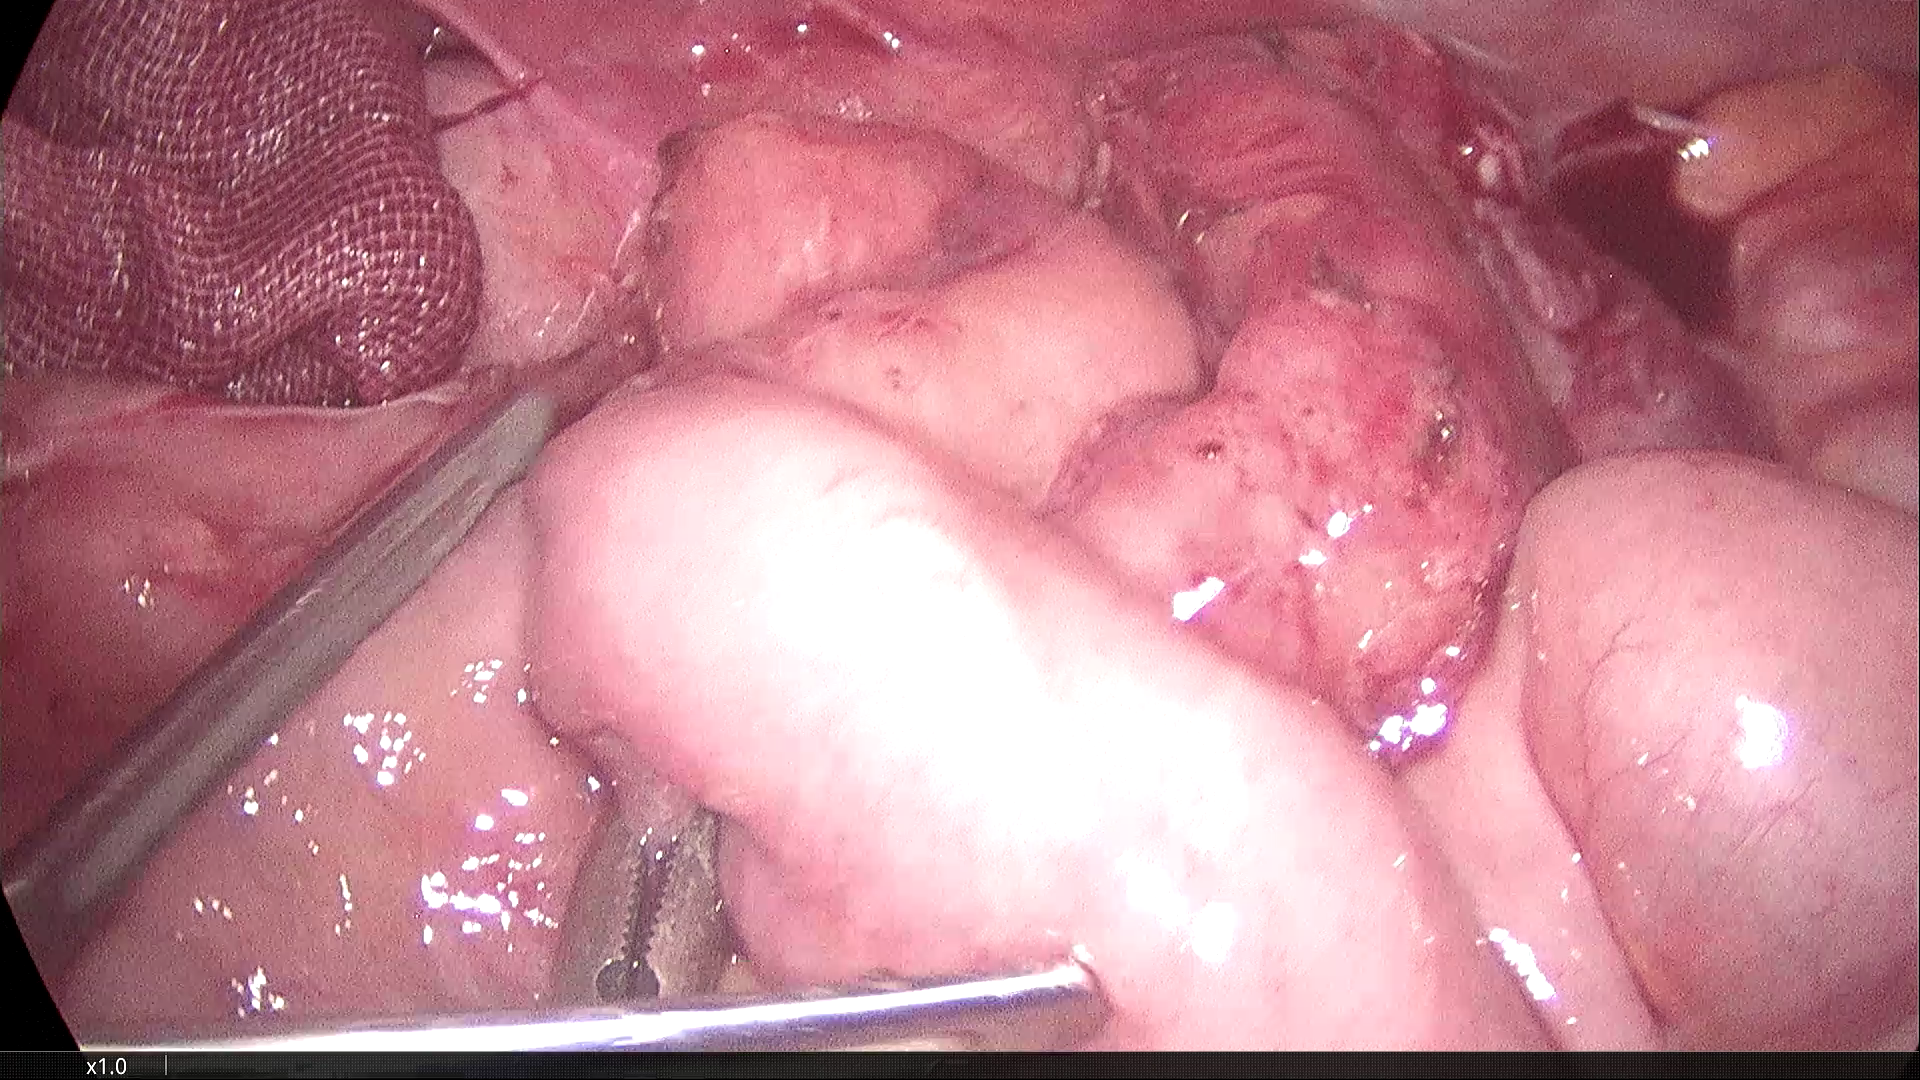

2021-3-31腹腔镜探查,脐部闭合穿刺置入腹腔镜,为观察孔。左下腹及下腹正中分别作操作孔,腹腔镜探查,腹膜光滑,腹腔无积液,胃肠道柔软,空回肠结肠无扩张。无游离大网膜,右下腹无游离肠襻,区域性的回肠肠襻为软膜样组织覆盖包裹,无明显炎症反应。包裹团块张力不高,内侧与乙状结肠系膜呈纤维组织粘连。锐性分离,无明显渗出。自后腹壁锐性切开包膜,显露其内迂曲回肠襻,形态大致正常,与包膜呈一般纤维组织性间隙,易于分离。包膜内肠管间有数条致密粘连纤维索带,予以切除。切除大部包膜组织,完全解放其中的回肠及阑尾远端部分。局部创面少许渗出,自回盲部顺序近端探查检视所有系膜小肠,见肠管及系膜自然正常形态,肠道畅通,未见憩室、肿物及外压扭转等病变。包膜包裹段回肠120cm,肠壁、系膜柔顺无损伤。直肠及盆腔未见明显异常,置腹腔引流管一根。

末段回肠为纤维软膜包裹

横结肠处大网膜消失,代以纤维软膜样组织。

乙状结肠与回肠襻包裹膜的纤维粘连

包裹回肠襻的纤维膜

剥离包裹纤维膜,松解受困的回肠襻。

松解后的效果图